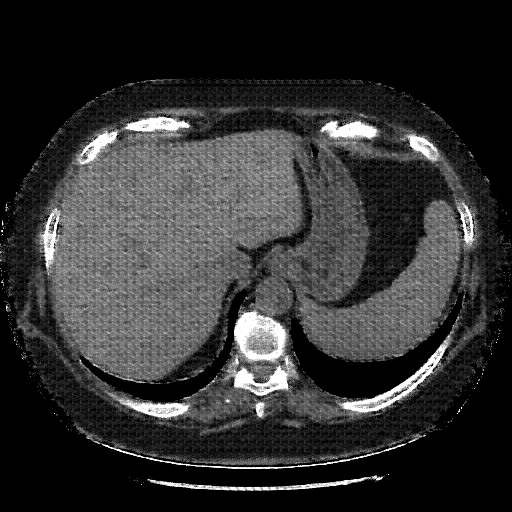

Generated VENOUS CT scan (A→B translation)

Full window (WL 1023.5, WW 4095 β†’ Low βˆ’1024, High +3071)

Actual HU range: [-1024.0, 981.6]

Lung window (WL -600, WW 1500 β†’ Low βˆ’1350, High +150)

Actual HU range: [-1350.0, 150.0]

Mediastinum window (WL 40, WW 400 β†’ Low βˆ’160, High +240)

Actual HU range: [-160.0, 240.0]